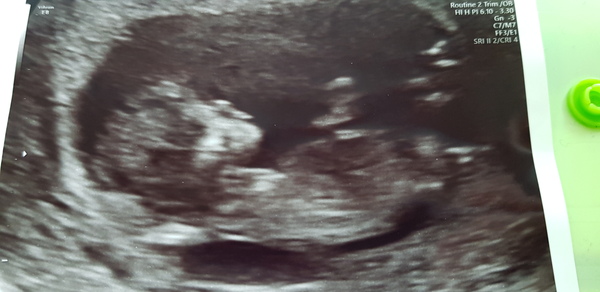

Well, I was less of a nervous wreck than I thought I would be this morning. I was a bit weepy before we went into the scan, then the computer was misbehaving! The sonographer rebooted it and scanned whilst waiting. She immediately went "There's a tenant in there!". 1st measurement was a bit small, but 2nd was alright and EDD is 24 May 2020. Baby kept kicking, then mimicked the position I was doing with my arm, then bounced up and down quite a bit. I think it's sinking in that this might actually be happening and it's not a dream...